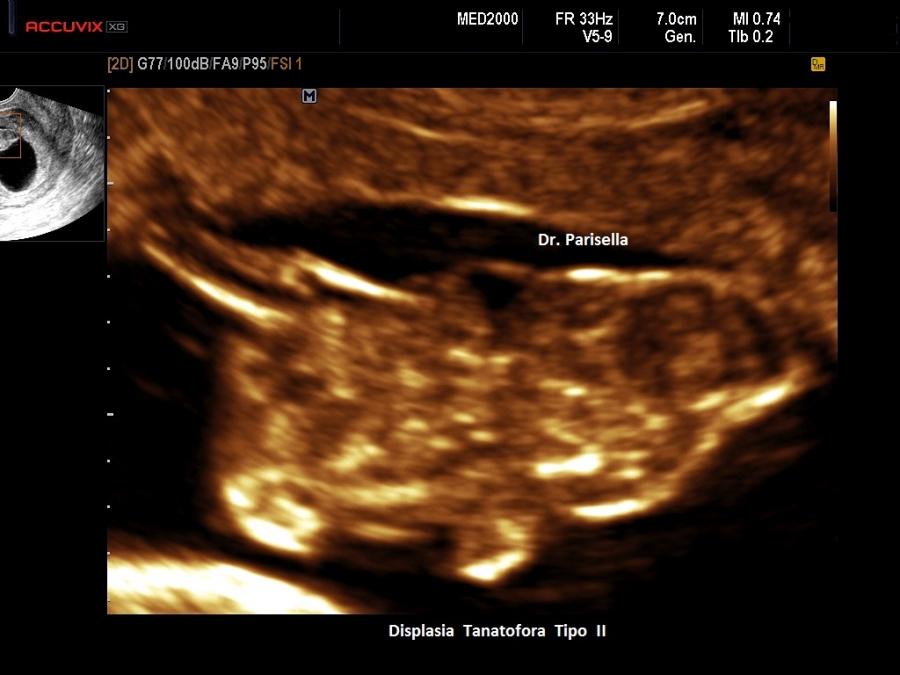

Un altro dato da valutare è il grado di curvatura ossea; le due principali condizioni che possono presentare in epoca prenatale un incurvamento delle ossa lunghe sono l'osteogenesi imperfetta e la displasia tanatofora tipo I (femori a cornetta di telefono).

Per quanto riguarda il rachide la Platispondilia (comunque non facilmente evidenziabile ecograficamente) è presente nella Displasia Tanatofora e nella Displasia Metatropica. Nell'Acondrogenesi tipo I si ha scarsa ossificazione dei corpi vertebrali e costantemente non si visualizza il sacro.

La misura della circonferenza toracica con un valore < 5° percentile è un indice di ipoplasia polmonare, causa di distress respiratorio nel neonato e indice di letalità. La biometria toracica e la morfologia toracica possono orientarci verso una particolare forma di displasia: se il torace è eccessivamente piccolo potrebbe trattarsi di una Displasia Tanatofora; se il torace è lungo e stretto potrebbe trattarsi di una Sindrome di Jeune; se le coste sono molto corte potrebbe trattarsi di una Sindrome coste corte con o senza polidattilia; se ci sono fratture costali potrebbe trattarsi di una Osteogenesi Imperfetta tipo II; se le coste sono fuse tra loro potrebbe trattarsi di una Displasia Spondilocostale.

Macrocefalia/Macrocrania è presente nella Acondroplasia, nella Displasia Tanatofora ( il tipo II è caratterizzato da “cranio a trifoglio” ), nell'Acondrogenesi. L'idrocefalia può essere una complicazione dell'Acondroplasia, dell'Osteogenesi Imperfetta e della Displasia Metatropica. Un cranio di consistenza molle (ossa wormiane) è sintomo costante di Osteogenesi Imperfetta anche se può essere presente in altre condizioni quali l'ipofosfatasia, la displasia cleido-cranica, etc. Nell'Ipofosfatasia vi può essere una aumentata ecogenicità della falce cerebrale.